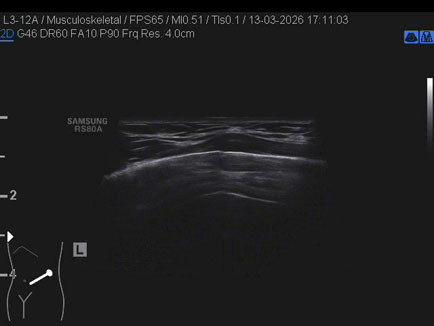

Data inserimento: 23/03/2026

Ecografia del: 13/03/2026

Strumento: Samsung

Sonda: Lineare

Commento all'esame: triplice frattura costale in ascellare anteriore sinistra in giovane dopo caduta con gli sci.

Conclusioni: triplice frattura costale (triple rib fracture).

Realizzazione: Dr. F. Pietro Tarini - Gubbio (PG)